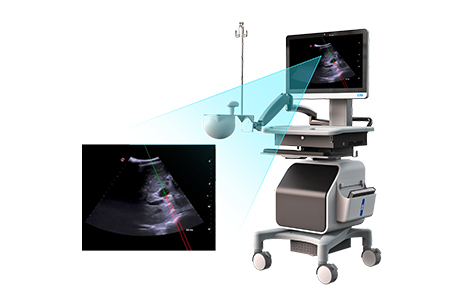

高端医疗器械

与临床现有结合DSA、、、、CT等医学影像的电磁导航设备不同,,此设备突破了电磁定位“卡脖子”技术,,,,通过将电磁导航与超声影像结合,,,,实现了介入手术的全程实时可视化。。。。该设备导航精度≤1.5mm,,,在涉及肝、、胆、、、肾、、、、前列腺等脏器的高难度深部穿刺中具有显著优势。。。。临床试验报告显示,,,使用该设备的一次进针穿刺成功率达98.96%。。。。同时,,该设备可降低高难度穿刺手术的学习难度,,,,提升TIPS(经颈静脉肝内门体静脉分流术)等四级手术的普及率。。。。